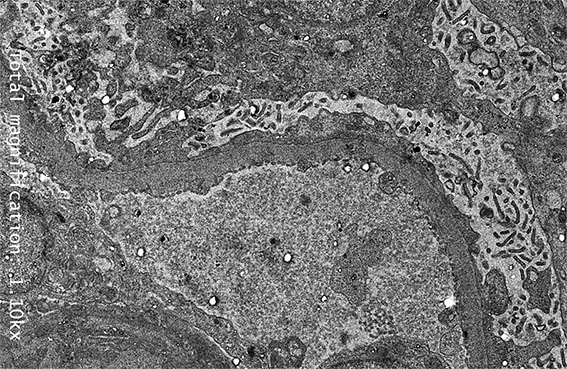

Figura 10. Daño podocitario difuso, con transformación microvellosa del citoplasma podocitario. ME, aumento original, X2.100.

Figura 11. ME, aumento original, X2.100.